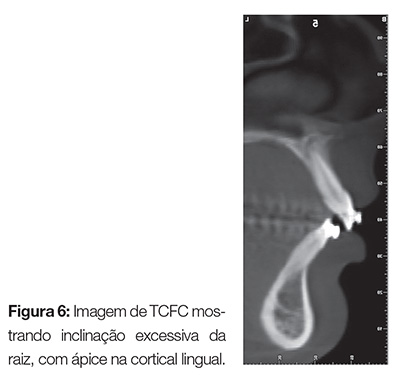

Alguns trabalhos já apontam as vantagens da tomografia cone beam para identificar a espessura óssea alveolar em relação aos dentes anteriores. Baysal et al.6 estudaram a posição dos incisivos inferiores e o suporte ósseo em pacientes Classe II média e Classe II com ângulo acentuado, e compararam os achados com pacientes de oclusão tipo Classe I. A espessura da parede vestibular foi significativamente maior nos pacientes de Classe I, quando comparados com os pacientes de Classe II.

O osso esponjoso estava mais fino e o ápice radicular mais próximo à cortical lingual em pacientes Classe II com ângulo acentuado do que quando comparado aos Classe II padrão. Isso tem uma implicância clínica, pois o limite do movimento dos incisivos inferiores em pacientes de Classe II com ângulo acentuado é limitado quando comparado aos pacientes de Classe II padrão. Tais achados de imagem somente são possíveis ao se analisar uma imagem 3D obtida a partir de uma TCFC (Fig. 6). Quando analisamos dentes retidos, existem evidências claras que o uso de imagens obtidas com TCFC pode levar à mudança no plano de tratamento, justificando sua indicação.